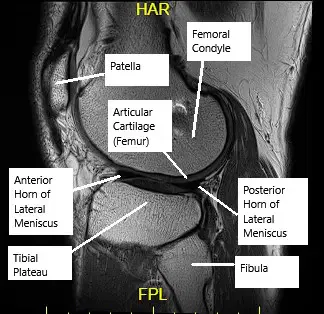

MRI of the knee showing articular cartilage.

Articular cartilage is a smooth, glistening tissue covering the ends of bones within a joint. In the knee, it cushions the femur, tibia, and patella, allowing for smooth, friction-free movement. Cartilage helps absorb shock, reduce friction, and distribute loads during activities like walking and running. However, due to its limited blood supply, damaged cartilage doesn’t heal effectively on its own, making it vulnerable to further injury and degeneration.

- MRI: The most effective tool for visualizing cartilage damage, providing detailed images of the cartilage, subchondral bone, and other soft tissues.